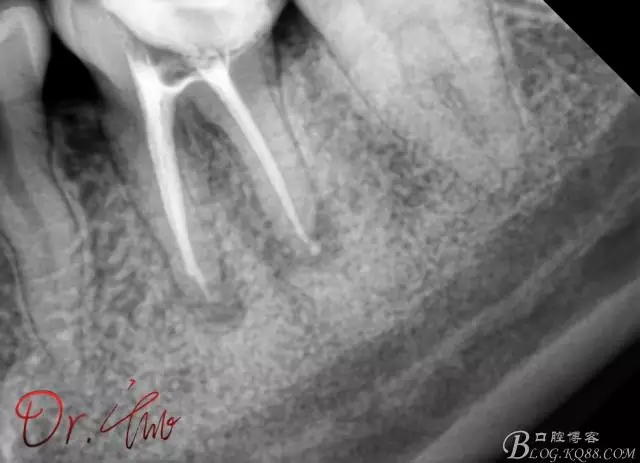

試主尖,近中頰側(cè)形成臺階

640.webp (7).jpg

試主尖,近中頰側(cè)再次拍片查看臺階位置及確定長度

640.webp (8).jpg

試主尖,近中頰側(cè)試主尖,此時手用銼02錐度的已擴到30號,可以明顯感覺到臺階位置,挫預(yù)彎后找好正確位置可順利到達根尖,但是機用銼就是下不去,也是郁悶